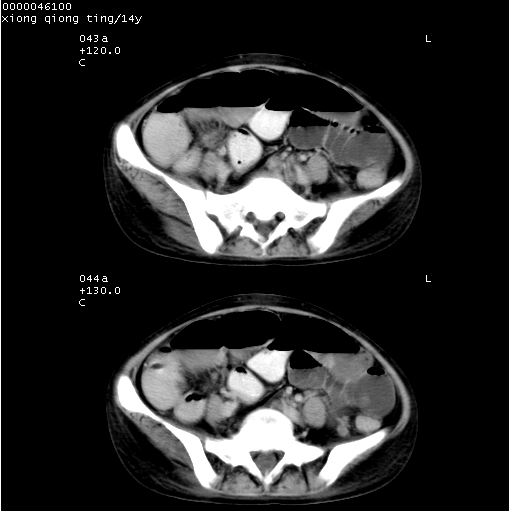

中下腹及盆腔ct轴位平扫+增强扫描(层厚10mm,螺距1.0,重建间隔10mm),图像如下:

(注:患儿检查当日上午9时口服胃肠道对比剂,下午3时许行ct扫描检查,未行对比剂直肠保留灌肠,检查当日患儿腹泻)

中下腹及盆腔ct轴位扫描(ps+ce)提示:腹部肠管明显充气扩张,并见数个不同宽度之气液平面;疑不全性肠梗阻或肠郁张。临床会诊考虑为患儿腹泻,肠郁张所致;后来未经特殊处理,患儿大便恢复正常,亦无腹胀。

临床出院诊断:1)结核性腹膜炎。2)腹膜后淋巴结结核。3)脂肪肝。